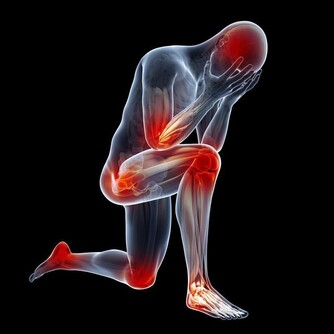

1.中指指甲凹陷:體內尿酸過多、肌肉痠痛。